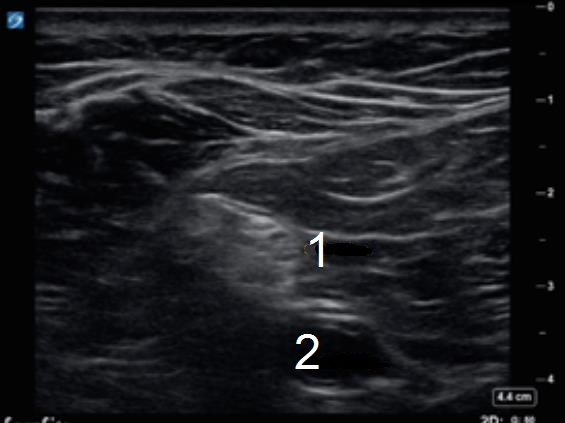

Popliteal Sciatic Nerve Image

Sciatic Nerve

Popliteal Artery